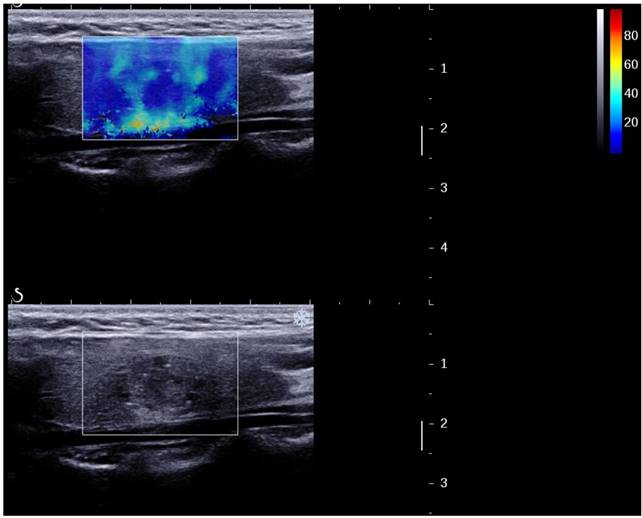

Figure 4

A papillary carcinoma missed by B-mode US (TI-RADS 4a) but suspicious by 2D SWE (S-Tmean=25.3 kPa).

J Cancer Image

Table 5 showed ROC curve analysis of these combination methods. B + 2D SWE, B-mode + 3D SWE, B + 2D + 3D SWE I had higher sensitivity and accuracy values than those of 3 singular methods and B + 2D + 3D SWE II, but had lower specificity values. On the contrary, B + 2D + 3D SWE II had higher specificity values than the other methods but lower specificity values except 2D SWE. Among them, B-mode ultrasound + 2D SWE had the highest sensitivity, NPV, accuracy and Youden's index (0.881, 0.788, 0.804 and 0.57) (Fig 4).